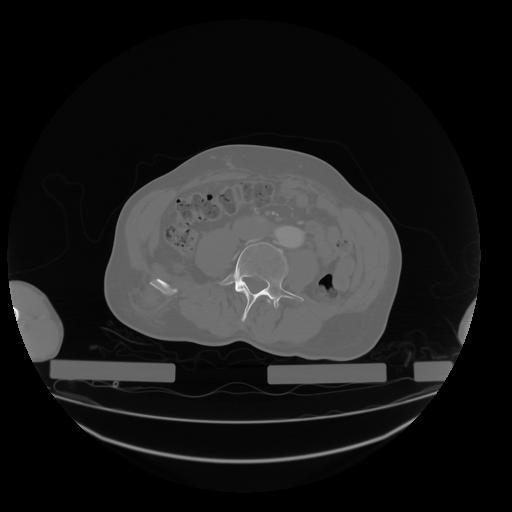

28 CUERPO,CE,Vol,2.0,CUERPO,,